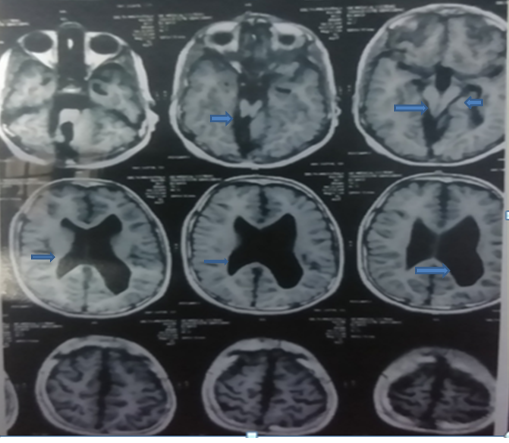

A 7 years old male child with global developmental delay presented with recurrent falls on the right side while walking for 15 days. He had 2 episodes of generalized tonic-clonic seizures 2 years ago for which he was taking sodium valproate at a dose of 20 mg/kg/day following which he was seizure-free. He also had occipital encephalocele at birth for which he was operated on day 2 of life. On examination, signs of cerebellar ataxia were present with ataxia involving the right side predominantly. Other systems were normal. MRI brain revealed supratentorial ventricular dilation, the parallelism of walls of 3rd ventricle with a diameter of 9.5 mm, grey matter heterotopias in the frontal lobe, distorted elongated 4th ventricle communicating with fluid spaces in post fossa on the right side and non-visualization of the right-sided cerebellar hemisphere (Figure 1).

Figure 1. MRI brain showing supratentorial ventricular dilation with distorted elongated 4th ventricle communicating with fluid spaces in post fossa on right side and non-visualization of the right sided cerebellar hemisphere with parallelism of walls of 3rd ventricle